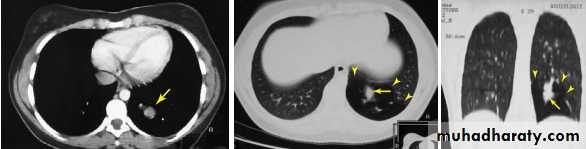

Computed tomography or CT is an imaging modality that produces cross-sectional images representing the X-ray attenuation properties of

the body.

A- CAT (computed axial tomorgaphy ) scan

Single-slice CT , Circular CT

The most straight forward way to image an entire volume is to scan a number of consecutive slices by circular tube–detector rotations alternated with small table shifts.

B- Spiral CT (Helical CT)

A technique that is widely used nowadays is helical CT.The X-ray tube rotates continuously around the

patient, just as in 2D CT. At the same time, the patient

is slowly translated through the gantry.

Multidetector spiral CT scan ( 4 , 8 , 16 slice , 32 slice , 64 ,128 and 256 slice) .

In modern CT scanners, the detector array consists of multiple detector rows, in order to measure several slices per rotation of the X-ray tube.Biologic effects and safety